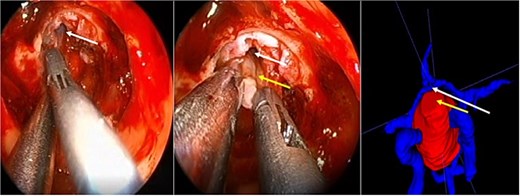

A 71-year-old woman who gradually began with bitemporal hemianopia, progressing to amaurosis of the right eye, adding diabetes insipidus. An MRI study obtained the following images (Fig. 1). 3D reconstruction was performed by manual segmentation to obtain the anatomy of the tumor and its vascular relationships. For this segmentation, it was necessary to splice T2, T1, Contrast, and 3D TOF sequences (Fig. 2). The importance of the reconstruction lies in being able to adequately observe most of the cerebral blood circle and its relationships with the tumor. At the time of carrying out the transnasal resection surgery and keeping in mind the proximity of the anterior communicating artery with the dorso-ventral region of the tumor, the capsule was resected with excessive caution to avoid generating excessive traction and thus avoiding injuries—important vascular (Fig. 3).

Surgical images. White arrow, anterior communicating artery. Yellow arrow, tumor capsule.